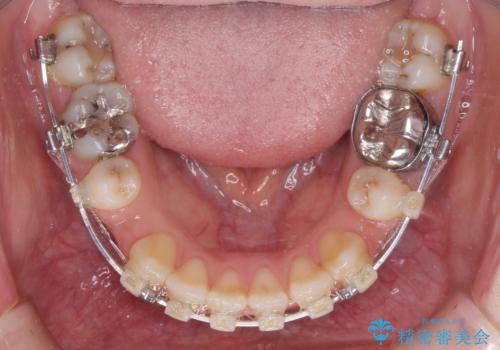

- 矯正装置

- 審美装置

治療は順調に進み、予定された期間で終了することができました。